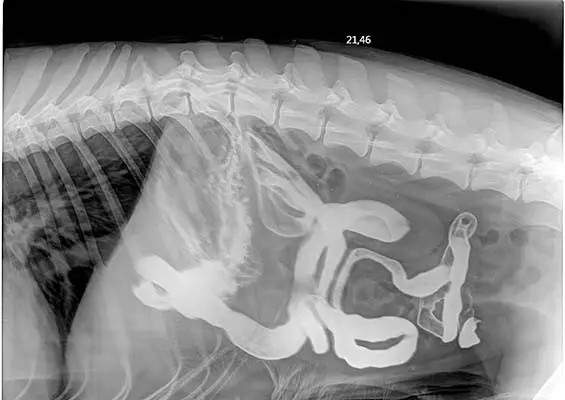

DIAGNOSTYKA

Dlaczego warto wykonywać dodatkowe badania obrazowe w diagnozowaniu chorób przewodu pokarmowego?